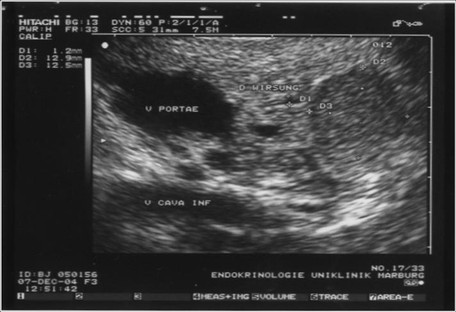

Die Sensitivität hängt von der Lokalisation des Tumors und der Fertigkeit des Untersuchers ab. Im Pankreaskopf wird sie bis zu 100 %, im Pankreaskorpus mit 78 % und im Pankreasschwanz mit 60 % angegeben. Die Nachweisgrenze der Insulinome liegt bei einem Tumordurchmesser von 2-

Endosonographie des Pankreas mit typischem echoarmen Befund eines Insulinoms.

Nach biochemischer Sicherung eines organischen Hyperinsulinismus durch einen Hungerversuch und Ausschluss eines metastasierten Insulinoms durch transabdominellen Ultraschall oder CT, sollte keine weitere präoperative Lokalisationsdiagnostik durchgeführt werden. Wie bereits erwähnt können durch intraoperativen Ultraschall und bidigitaler Palpation der gesamten Drüse nahezu alle Insulinome identifiziert werden. Eine Ausnahme besteht bei einer laparoskopisch geplanten Operation. Dort sollte präoperativ zusätzlich eine Endosonographie durchgeführt werden, um die intrapankreatische Lage des Tumors und seine Beziehung zum Ductus pancreaticus festzulegen. Zudem kann bei der laparoskopischen Technik keinesfalls auf die intraoperative, hier dann laparoskopische Sonographie verzichtet werden. Nur so lässt sich der Verlust der Palpation bei der laparoskopischen Operation kompensieren.